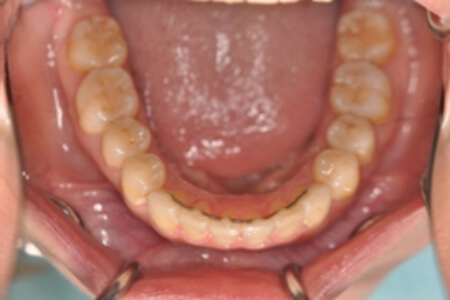

動的治療終了時

症例 症例 症例 症例

治療としては、非抜歯の上、セルフライゲーションブラケット装置(デーモンシステム)とマウスピース矯正装置(インビザライン)で歯の配列を行いました。

同時に顎間ゴムにて咬合関係の改善を行いました。

治療期間は2年11か月でした。